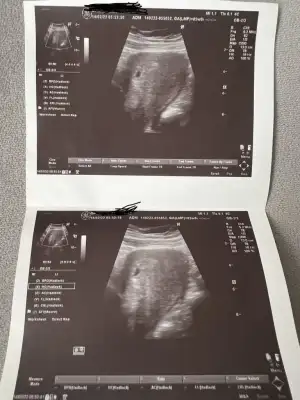

Bu akşam Çok fazla kanamam başladı. Dışarıdaydım Çay bardağından dökülür gibi bi anda kan boşaldı. Şimdi devam ediyor. Gebze MedicalPark aciline geldik hemen mahmut diye bi kadın doğumcu var gerçekten rezalet biri. Bebeğin kalbi atıyor dedi 140 Mış ama tam anlamıyla 1 buçuk dakikalık muayenesi ile hiç tatmin olmadım.bana atıyor diye gösterdi ama kıpırtı bile yoktu daha önce nasıl attığını gördüm gözümle. Kanama alanı var mı dedim evet kim dedi var diyor. Pıhtı varmış kesenin kenarında. Bebeğin düşmek istiyor, yat ve tabak bile kaldırma dedi.

Böyle canım işte. İnşallah belki sen anlarsın.

Ben kese boyutunu göremedim sanırım olcmemis olcunce kesenin basinda sonunda çarpı işareti falan oluyor ama dikkatimi çeken senin de ultrasonda 5+0 gozukmus benim de o gün 5+0 gozukmustu halbuki 5+2 ydim